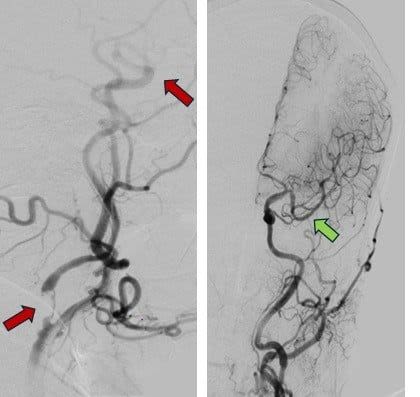

Ngay lập tức, các bác sĩ tiến hành dùng thuốc tiêu sợi huyết, chụp CTA rồi tái thông động mạch não giữa. Chỉ trong 20 phút, dòng máu não được tái lập.

Trường hợp thứ hai là anh B. 30 tuổi, khi đang tham gia đá bóng tại xã Củ Chi bỗng thấy chóng mặt, mất thăng bằng rồi gục xuống sân. Sau hai mươi phút anh được đưa tới Bệnh viện đa khoa Xuyên Á, huyết áp tăng vọt 200/100 mmHg, MRI ghi nhận nhồi máu tiểu cầu phải.

Bác sĩ quyết định tiêm thuốc tiêu sợi huyết đường tĩnh mạch, tái thông mạch máu tắc nghẽn. Chỉ vài phút sau, bệnh nhân hồi phục thăng bằng và có thể đi lại. Sau bảy ngày điều trị, anh B. phục hồi hoàn toàn.